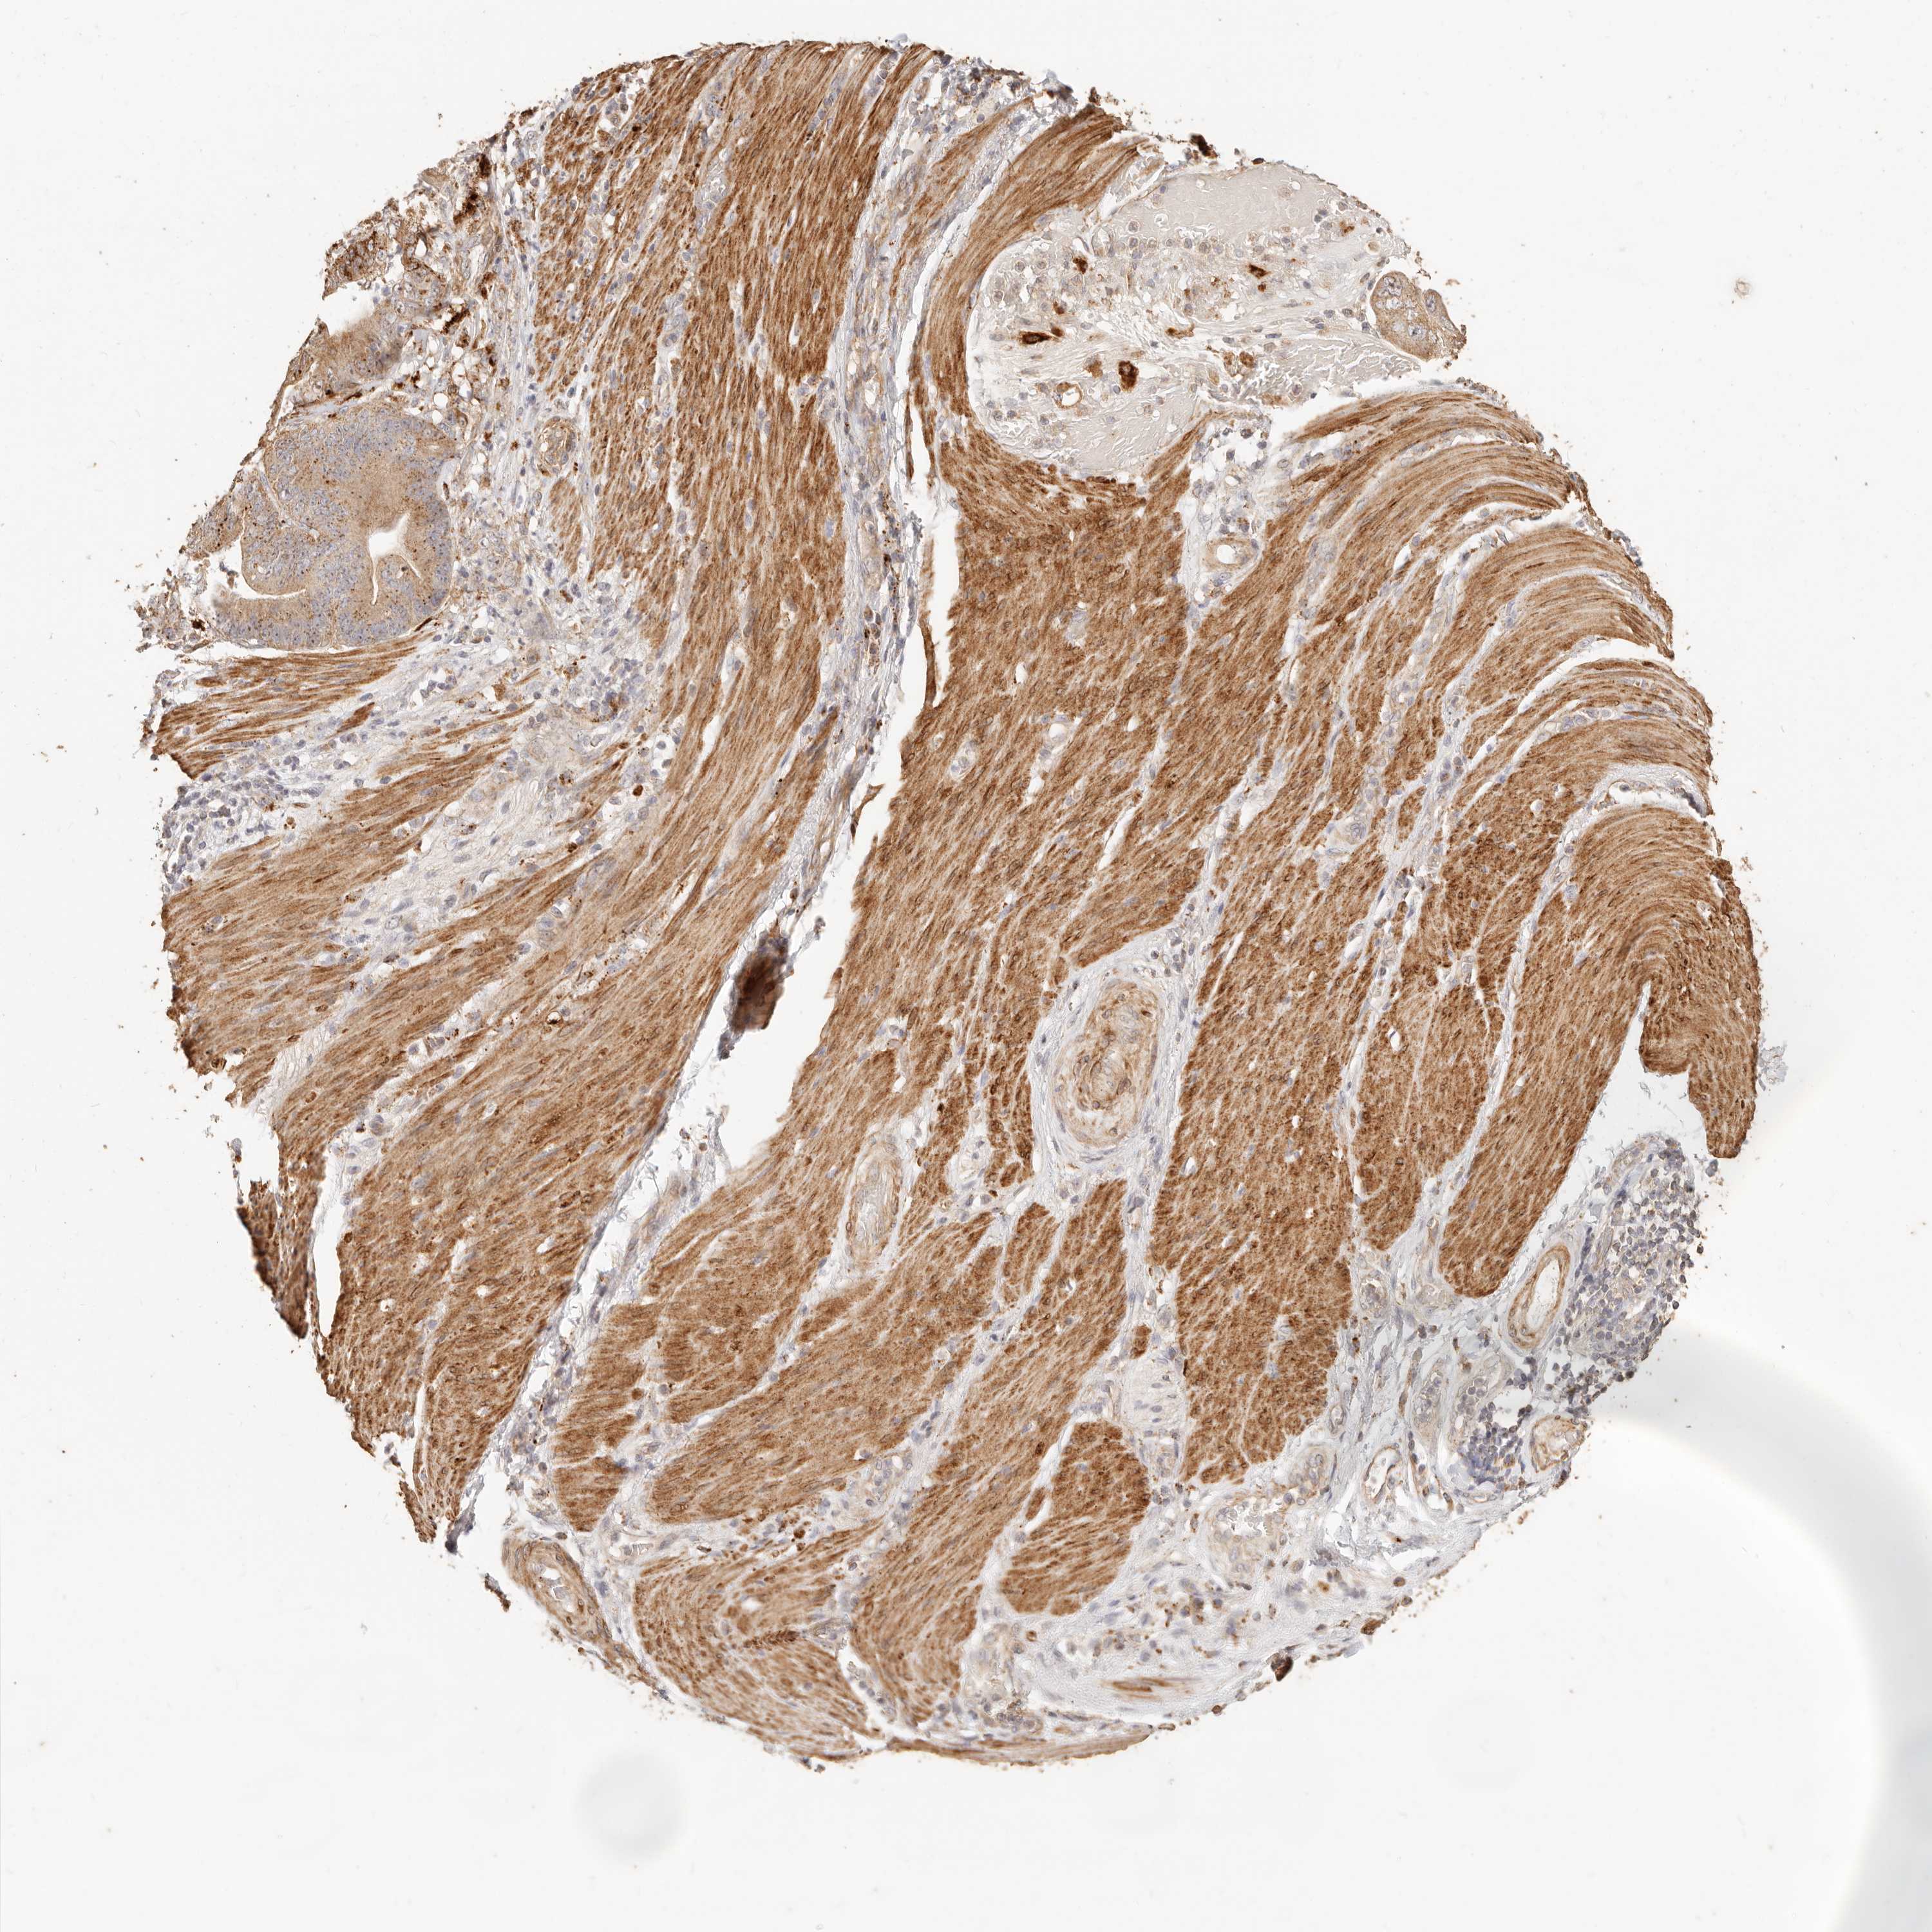

STOMACH CANCER - Protein expressioni

A mouse-over function shows sample information and annotation data. Click on an image to view it in a full screen mode. Samples can be filtered based on level of antibody staining by selecting one or several of the following categories: high, medium, low and not detected. The assay and annotation is described here.

Note that samples used for immunohistochemistry by the Human Protein Atlas do not correspond to samples in the TCGA dataset.

Antibody stainingi

Antibody staining in the annotated cell types in the current human tissue is reported as not detected, low, medium, or high, based on conventional immunohistochemistry profiling in selected tissues. This score is based on the combination of the staining intensity and fraction of stained cells.

Each image is clickable and will lead to virtual microscopy that enables deeper exploration of all samples and also displays staining intensity scores, fraction scores and subcellular localization as well as patient and tissue information for each sample.

Antibody HPA004912

Antibody HPA013350

Antibody CAB012209

Staining

High

Medium

Low

Not detected

Intensity

Strong

Moderate

Weak

Negative

Quantity

>75%

75%-25%

<25%

None

Location

Nuclear

Cytoplasmic/membranous

Cytoplasmic/membranous,nuclear

Adenocarcinoma, NOS